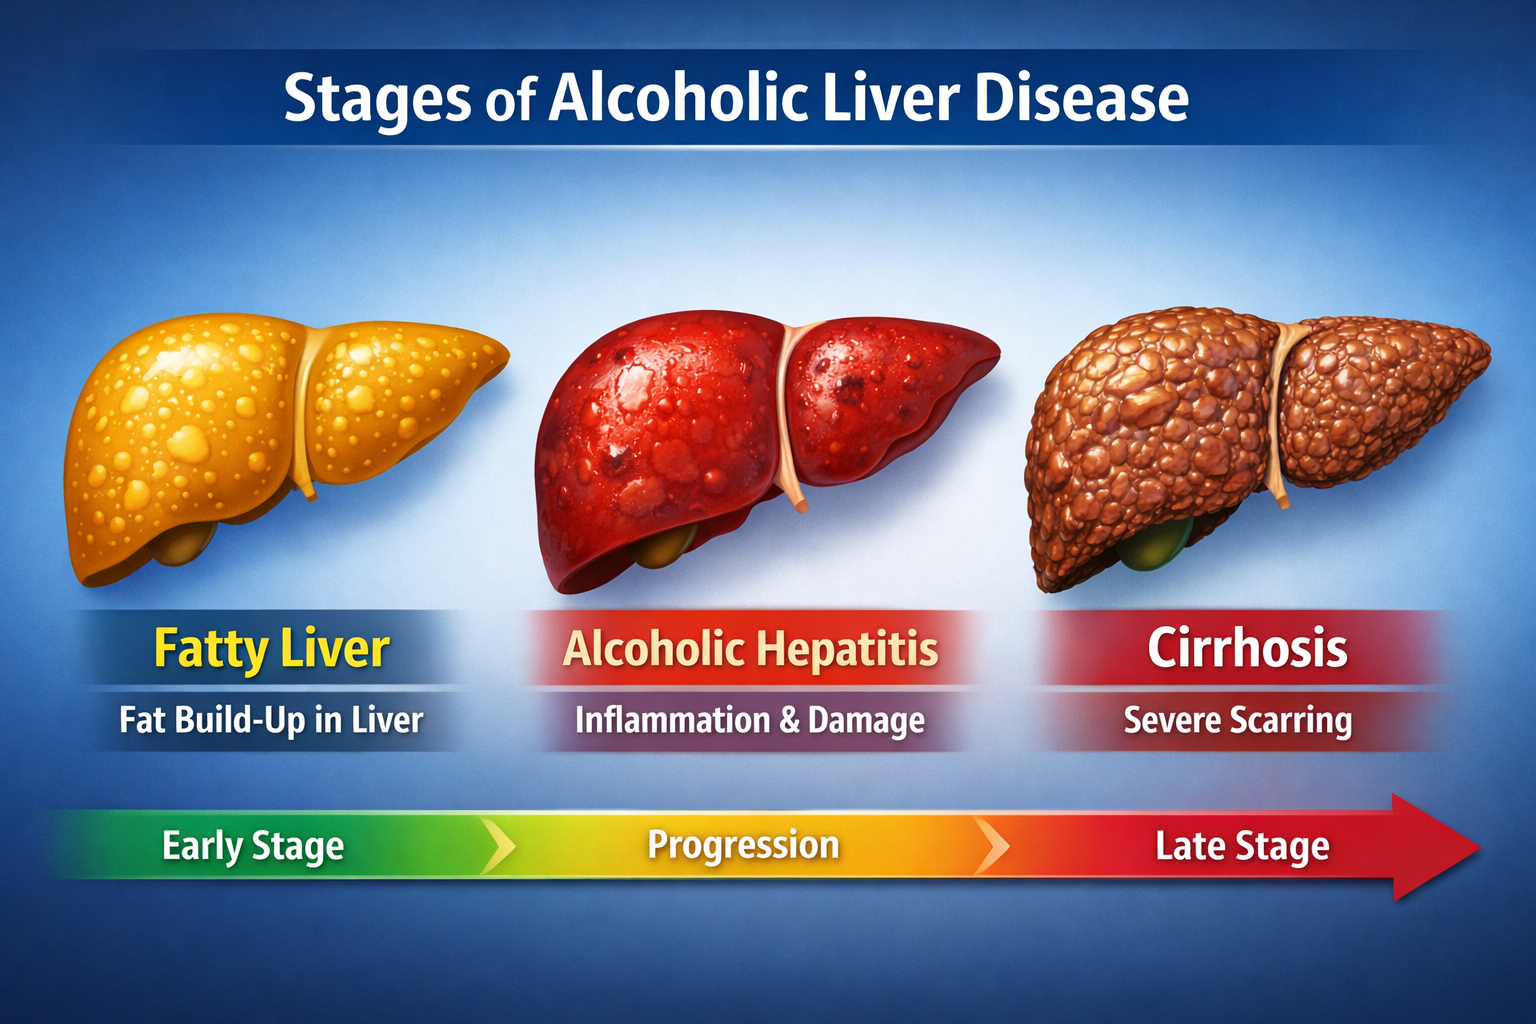

Looking for Hepatitis C treatment in Hyderabad? Dr Rahul Dubbaka offers advanced antiviral therapy with 95%+ cure rates at People’s Hospital, Pragathi Nagar. Book your consultation today at +91 9100921514. Hepatitis C is a viral infection that primarily affects the liver and can silently damage it over time. If left untreated, it may lead to serious complications such as cirrhosis, liver failure, and even liver cancer. The good news is that with modern medical advancements, Hepatitis C is now highly curable with effective antiviral medications.

Over time, chronic Hepatitis C can cause progressive liver inflammation, leading to fibrosis (scarring), cirrhosis, and increased risk of liver cancer.

Complications of Untreated Hepatitis C

If not treated, Hepatitis C may lead to:

Liver cirrhosis

Liver failure

Portal hypertension

Ascites

Liver cancer (Hepatocellular carcinoma)

Early treatment prevents these complications and improves life expectancy.

Importance of Early Treatment

Many patients delay treatment due to lack of symptoms. However, early treatment:

Prevents irreversible liver damage

Reduces risk of transmission

Improves overall quality of life

Offers complete cure in most cases

Timely intervention makes a significant difference.